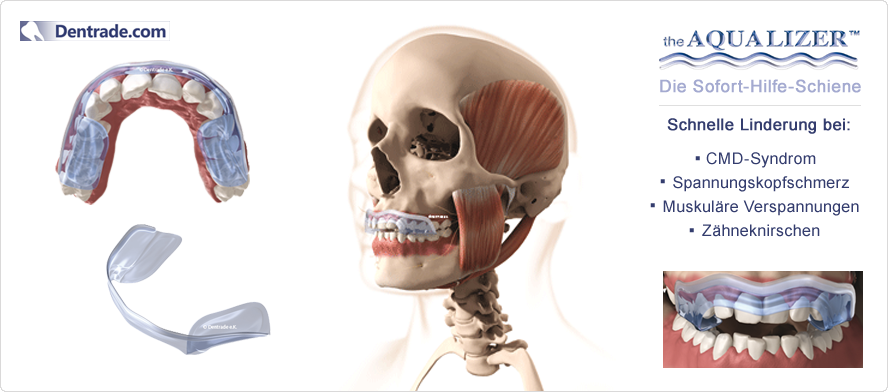

Aqualizer™ - це єдина гідростатична накусочна шина, яка може бути застосована при лікуванні будь-якого пацієнта без попередньої підготовки та зуботехнічних робіт.

Завдяки водяному наповненню аквалайзер автоматично пристосовується до анатомічних особливостей пацієнта. Аквалайзер також добре зарекомендував себе при анамнезі та клінічній функціональній діагностиці як засіб діагностики та тимчасовий (лікувальний) засіб. Аквалайзер моментально компенсує неправильний прикус та встановлює збалансовану нервово-м`язову позицію нижньої щелепи. Позиція щелепи, при якій м`язи розслаблені, досягається за декілька хвилин. Для виготовлення нервово-м`язевого регістрату рекомендується тривалість носіння 1-2 тижні. За допомогою оклюзійних відбитків на пластмасовій поверхні аквалайзера візуалізується надмірний тиск при накусуванні чи скреготанні. Гідростатичний ефект також проявляється при застосуванні аквалайзера одночасно з іншою шиною.

Функціонування аквалайзера

Аквалайзер дизайн УЛЬТРА (Aqualizer ULTRA)

Аквалайзер дизайн СЛІМ (Aqualizer SLIM)

Види аквалайзерів

Доступні три різні різні види аквалайзерів: Aqualizer classic, Aqualizer ultra, Aqualizer ultra MINI для дітей.